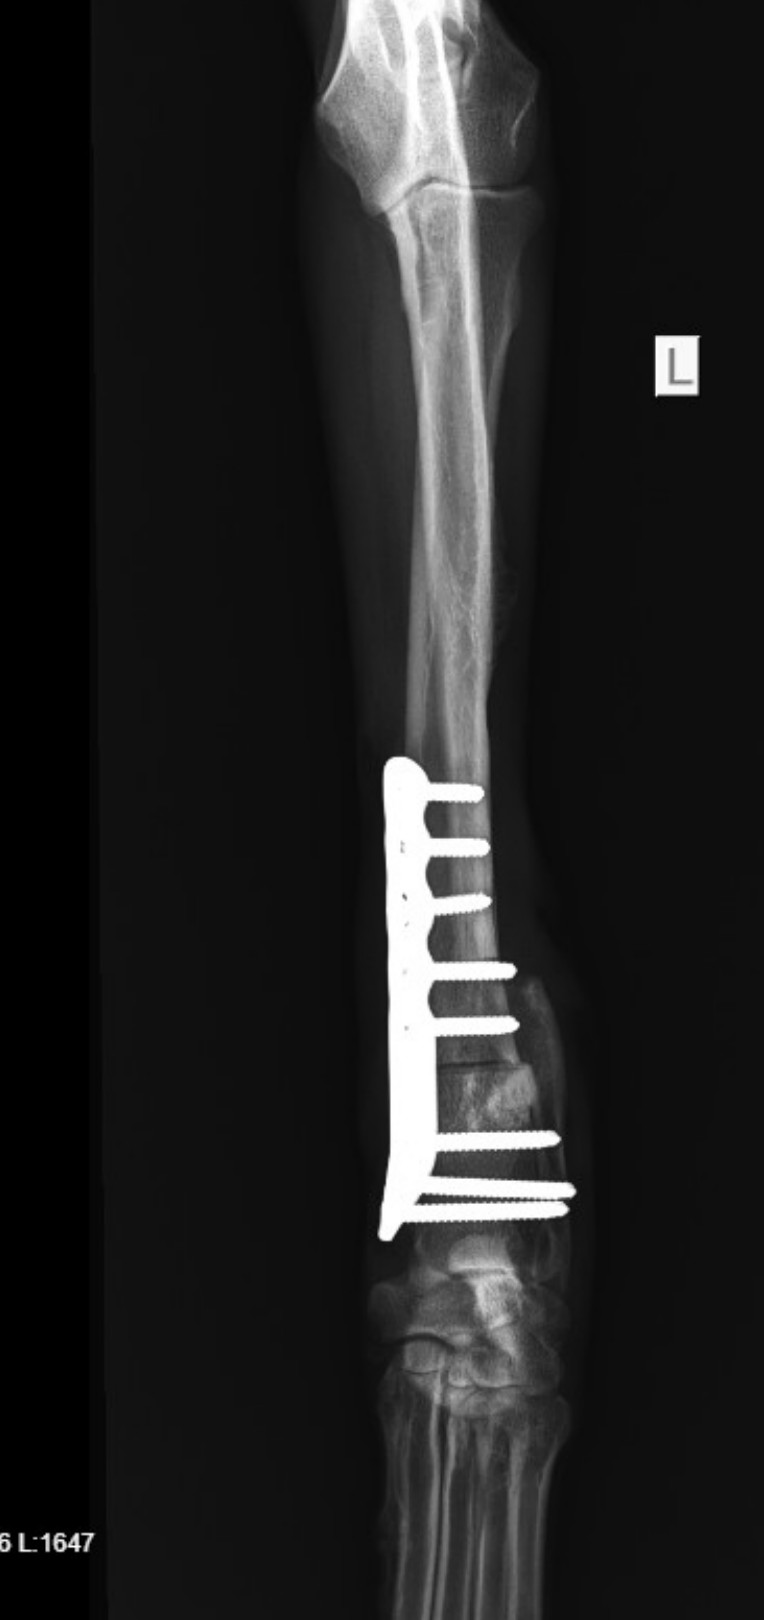

Im Refugio abgegeben, weil er nicht länger zu gebrauchen war: Joselito hat seinem Besitzer treu gedient, war schnell und gehorsam. Doch dann verletzte er sich bei der Jagd und brach sich das linke Vorderbein.

Ein Besuch beim Tierarzt kam für den Jäger nicht infrage. Viel zu teuer! Mehrere Wochen versuchte Joselito unter großen Schmerzen, weiter nützlich zu sein, doch mit dem unbehandelten Bruch konnte er nicht mehr rennen.

Die Tierärztin wollte den Bruch nicht mehr operieren, weil sich bereits ein Callus gebildet hatte und sie den Knochen erneut hätte brechen müssen. Und Joselito war weiterhin tapfer.

Nach einigen Untersuchungen in der Tierklinik stand fest, dass eine OP unumgänglich sei. Joselito kam unters Messer, und dabei wurde festgestellt, dass es um sein Bein weit schlimmer stand als befürchtet. Schon die erste OP hat knapp viertausend Euro verschlungen, und es werden noch zwei weitere benötigt, damit Joselito endlich wieder schmerzfrei durchs Leben gehen kann.